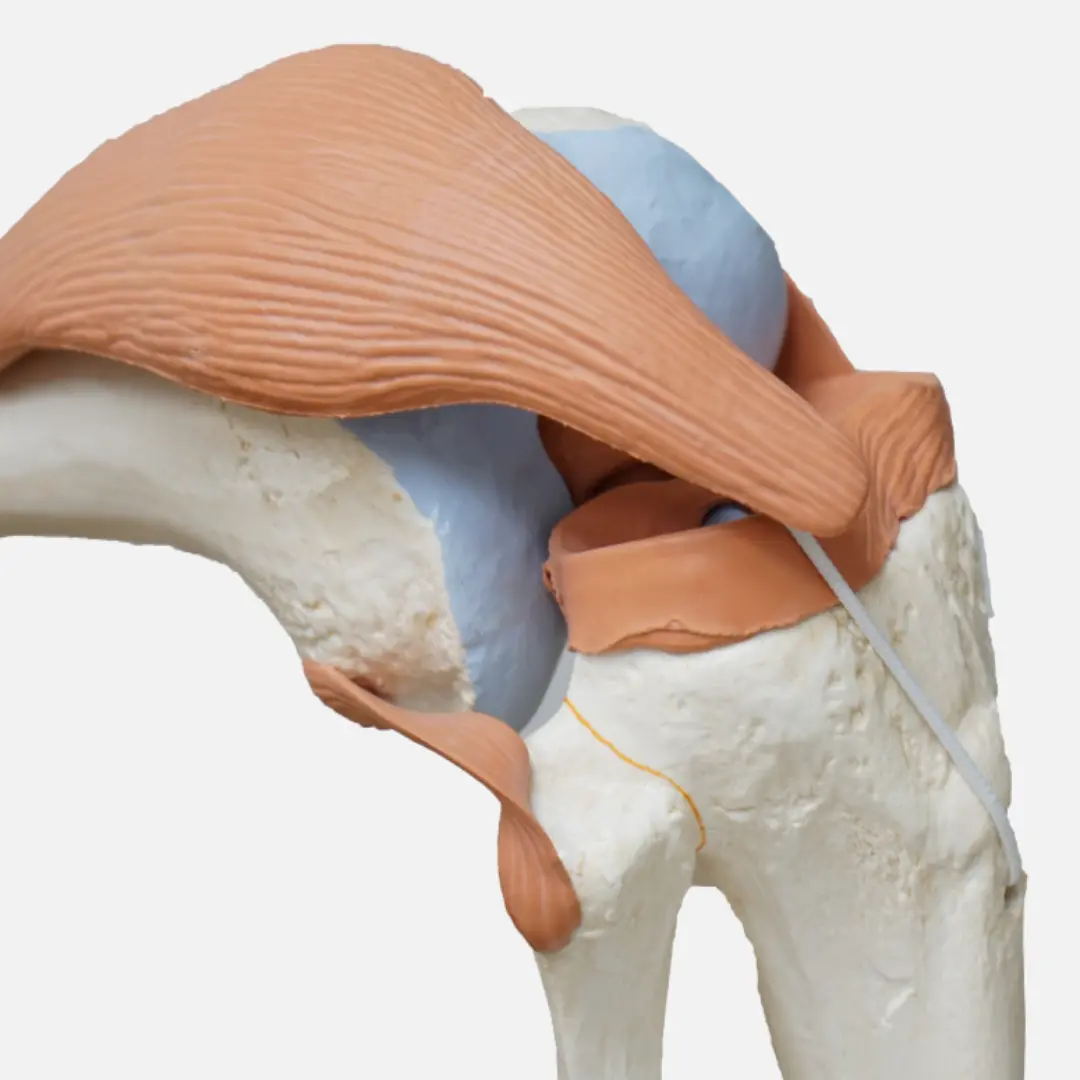

글루코사민(Glucosamine)은 우리 몸에서 자연적으로 생성되는 아미노당의 일종이에요. 주로 연골, 인대, 힘줄, 피부 등 결합 조직에 풍부하게 존재하며, 특히 관절 연골의 주요 구성 성분인 프로테오글리칸(Proteoglycan)과 히알루론산(Hyaluronic acid)의 중요한 재료가 됩니다.

연골은 관절에서 뼈와 뼈가 직접 부딪히는 것을 막아주고, 충격을 흡수하며, 부드러운 움직임을 가능하게 하는 쿠션 역할을 합니다. 이 연골은 콘드로이틴과 함께 글루코사민을 통해 건강하게 유지될 수 있어요. 하지만 나이가 들거나, 과체중, 과도한 운동 등으로 인해 연골이 손상되거나 글루코사민 생성 능력이 떨어지면 연골이 닳아 없어지고 탄력을 잃게 됩니다. 이는 결국 관절 통증과 염증을 유발하는 퇴행성 관절염으로 이어질 수 있어요.

- 연골 구성 성분 보충: 연골의 주요 구성 요소인 프로테오글리칸과 히알루론산 생성을 돕습니다.

- 연골 손상 억제: 연골을 파괴하는 효소의 활성을 억제하여 연골 손상을 늦추는 데 기여할 수 있습니다.

- 관절 윤활액 생성 촉진: 관절액은 관절의 마찰을 줄여 부드러운 움직임을 돕는데, 글루코사민이 이 생성에 기여할 수 있습니다.